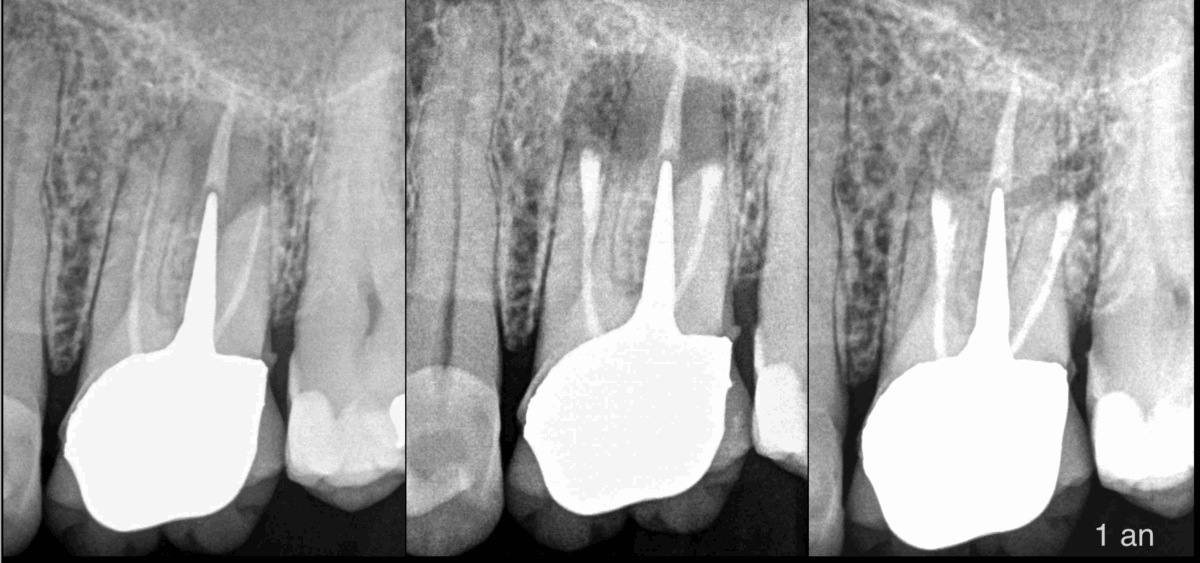

👑 𝐃𝐞́𝐩𝐨𝐬𝐞𝐫 𝐮𝐧𝐞 𝐜𝐨𝐮𝐫𝐨𝐧𝐧𝐞, 𝐜’𝐞𝐬𝐭 𝐩𝐞𝐫𝐝𝐫𝐞 𝐝𝐮 𝐜𝐚𝐩𝐢𝐭𝐚𝐥 𝐝𝐞𝐧𝐭𝐚𝐢𝐫𝐞.

🛠️ 𝐃𝐞́𝐩𝐨𝐬𝐞𝐫 𝐮𝐧 𝐚𝐧𝐜𝐫𝐚𝐠𝐞, 𝐜’𝐞𝐬𝐭 𝐩𝐞𝐫𝐝𝐫𝐞 𝐝𝐮 𝐜𝐚𝐩𝐢𝐭𝐚𝐥 𝐝𝐞𝐧𝐭𝐚𝐢𝐫𝐞.

🦷 𝐎𝐫 𝐥𝐞 𝐜𝐚𝐩𝐢𝐭𝐚𝐥 𝐝𝐞𝐧𝐭𝐚𝐢𝐫𝐞 𝐫𝐞𝐬𝐭𝐚𝐧𝐭, 𝐞𝐬𝐭 𝐝𝐢𝐫𝐞𝐜𝐭𝐞𝐦𝐞𝐧𝐭 𝐥𝐢𝐞́ 𝐚̀ 𝐥𝐚 𝐝𝐮𝐫𝐞́𝐞 𝐝𝐞 𝐯𝐢𝐞 𝐝𝐞 𝐥𝐚 𝐝𝐞𝐧𝐭.